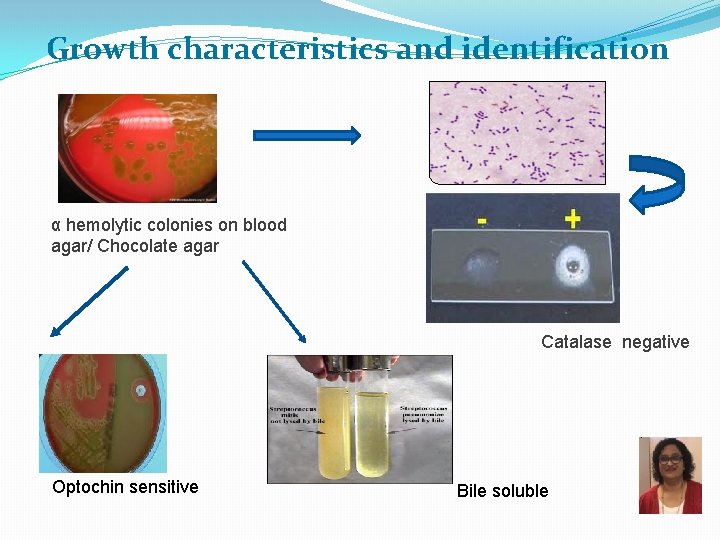

Growth characteristics and identification α hemolytic colonies on blood agar/ Chocolate agar Catalase negative Optochin sensitive Bile soluble

Pneumococcal Pneumonia - Diagnosis �Microscopy – Gram Stain �GPDC, lancet-shaped �Culture – blood agar � -hemolytic �Optochin (P disk) sensitivity �Catalase negative �Bile soluble �Susceptible to lysis P �Antimicrobial sensitivity test �PCR Optochin disc test Res Sus Bile solubility 21